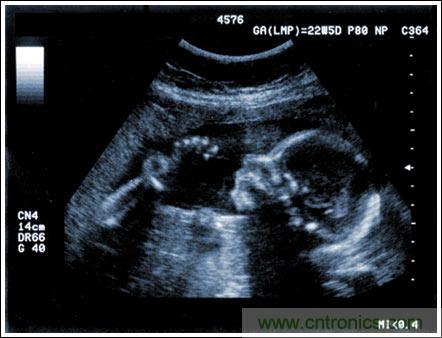

通過發(fā)射超聲能量進(jìn)入人體,接收并處理返回的反射信號(hào),相控陣超聲系統(tǒng)可以生成體內(nèi)器官和結(jié)構(gòu)的圖像,映射血液流動(dòng)和組織運(yùn)動(dòng),同時(shí)提供高準(zhǔn)確度的血流速度信息。傳統(tǒng)設(shè)計(jì)中,構(gòu)建這樣的成像系統(tǒng)需要大量的高性能相控陣發(fā)射器和接收器,使得車載設(shè)備體積龐大且價(jià)格昂貴。近年來(lái),隨著集成工藝的進(jìn)步,設(shè)計(jì)人員能夠獲得小尺寸、低成本而且高度便攜的成像系統(tǒng)方案,并可達(dá)到接近大型成像設(shè)備的性能指標(biāo)。而新的設(shè)計(jì)挑戰(zhàn)依然存在,即在進(jìn)一步提高方案集成度的同時(shí)提高系統(tǒng)性能和診斷能力。